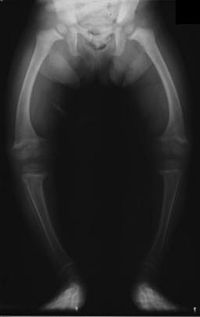

Ad:  rickets1.jpg

Gösterim: 2387

Boyut:  11.4 KB

Organizmada yeteri kadar kalsiyum tuzu bulunmaması nedeniyle kemiklerin gelişememesi ve normal sertlikte olmadıklarından şekillerinin bozulması biçiminde ortaya çıkan hastalık. Büyüme ve özellikle ilk çocukluk çağında görülen bir hastalıktır. Raşitizme tutulmuş çocuk aşırı terler, kaslar küçülür ve yumuşar, bıngıldağı kapanmaz, yürümesi gecikir, giderek kemiklerinde ve dişlerinde yapı bozuklukları ortaya çıkar. Çok eski zamanlardan beri bilinmesine karşın hastalığın tanımı ilk kez 1650'de İngiliz hekimi Glisson tarafından yapılmıştır. Genellikle yeteri kadar beslenemeyen küçük çocuklarda görülür. Buna karşılık 8-10, 14-17 yaşları arasında görülen buluğ çağı raşitizmi de vardır. Hastalığı hazırlayan etkenler iç ve dış etkenler olarak ikiye ayrılır. İç etkenler, kalıtım, erken doğum, anneden alınan bir mikrop, ikizlik, annenin frengi, verem gibi bir hastalığa yakalandığı sırada çocuk doğurması, organizmada vitamin oluşmasını engelleyici etkenler vb.dir. Dış etkenlerin başında ise güneşsizilk gelir. Örneğin Akdeniz ülkelerinde raşitizme, soğuk, nemli ve az güneş gören kuzey ülkelerine göre daha az rastlanır. Bunun dışında büyük kentlerin sisli, dumanlı havası ve yetersiz beslenme de dış etkenler arasında sayılabilir. İç ve dış etkenler yalnızca hastalığa elverişli bir ortam hazırlarlar. Raşitizmin gerçek yaratıcısı ise, vücuttaki D vitamini noksanlığıdır. Bu nedenle eksikliği ya da yokluğu kalsiyum ve fosforun vücut tarafından alınamaması ve raşitizm hastalığının ortaya çıkması sonucunu doğurur. Tedavi sırasında hasta temiz hava, bol ışık ve güneşten faydalanabileceği bir ortamda tutulmalı, besinlerine dikkat edilmeli, D vitamini noksanlığını giderecek önlemler (örneğin balıkyağı içirmek) alınmalıdır. Raşitizm, fazla geç kalınmazsa tedavi edilebilen bir hastalıktır.

Raşitizm, çoğunlukla D vitamini eksikliğine bağlı olan, genellikle 6 aylık-18 aylık çocuklarda görülen kemik hastalığıdır. Kemik oluşumunun tam olmaması nedeniyle tedavisi geciktirilmiş, ihmal edilmiş vakalarda uzun kemiklerde şekil bozukluğu meydana getirir.

Günümüzde ender rastlanan bir hastalık olan, oysa 20. yüzyıl başlarında Kuzey Avrupa ülkelerinde doğan çocukların yaklaşık %90'ının 4 yaşına gelmeden ölmelerine yol açan raşitizm, omurga, kol ve bacak kemiklerinde biçim bozukluklarına yol açar. Başlıca nedeni güneş yetersizliğine bağlı D vitamini eksikliğidir. Çok ender rastlanan bir nedeni de, bazı böbrek borucukları hastalıklarıdır. D vitamini eksikliğinden kaynaklanan raşitizm, biçim bozuklukları bırakarak kendiliğinden iyileşme gösterir. D vitamini iyileşmeyi sağlarsa da, doğuştan başlanarak 18. aya ya da 2 yaşına kadar D vitamini vermek yoluyla ortaya çıkmasını önlemek daha doğru bir yöntem olur.